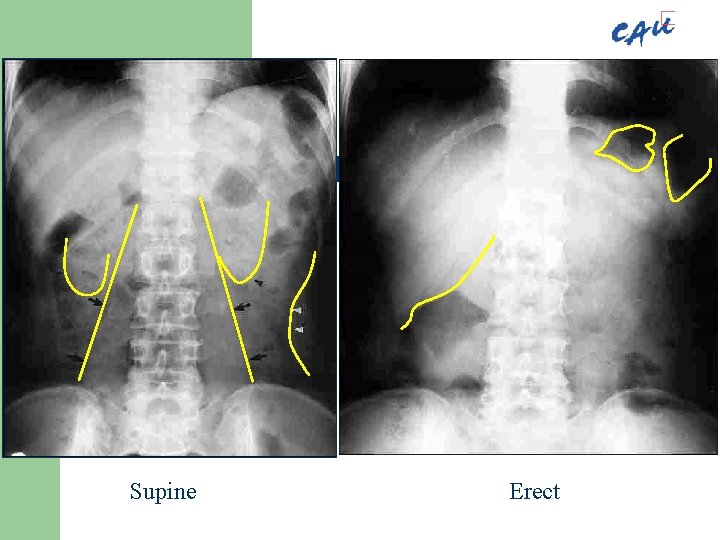

Introduction l l Supine Erect l Lateral decubitus

Introduction l l Supine Erect – – l Lateral decubitus Transtable lateral 반드시 양측 횡격막을 포함

Supine Erect